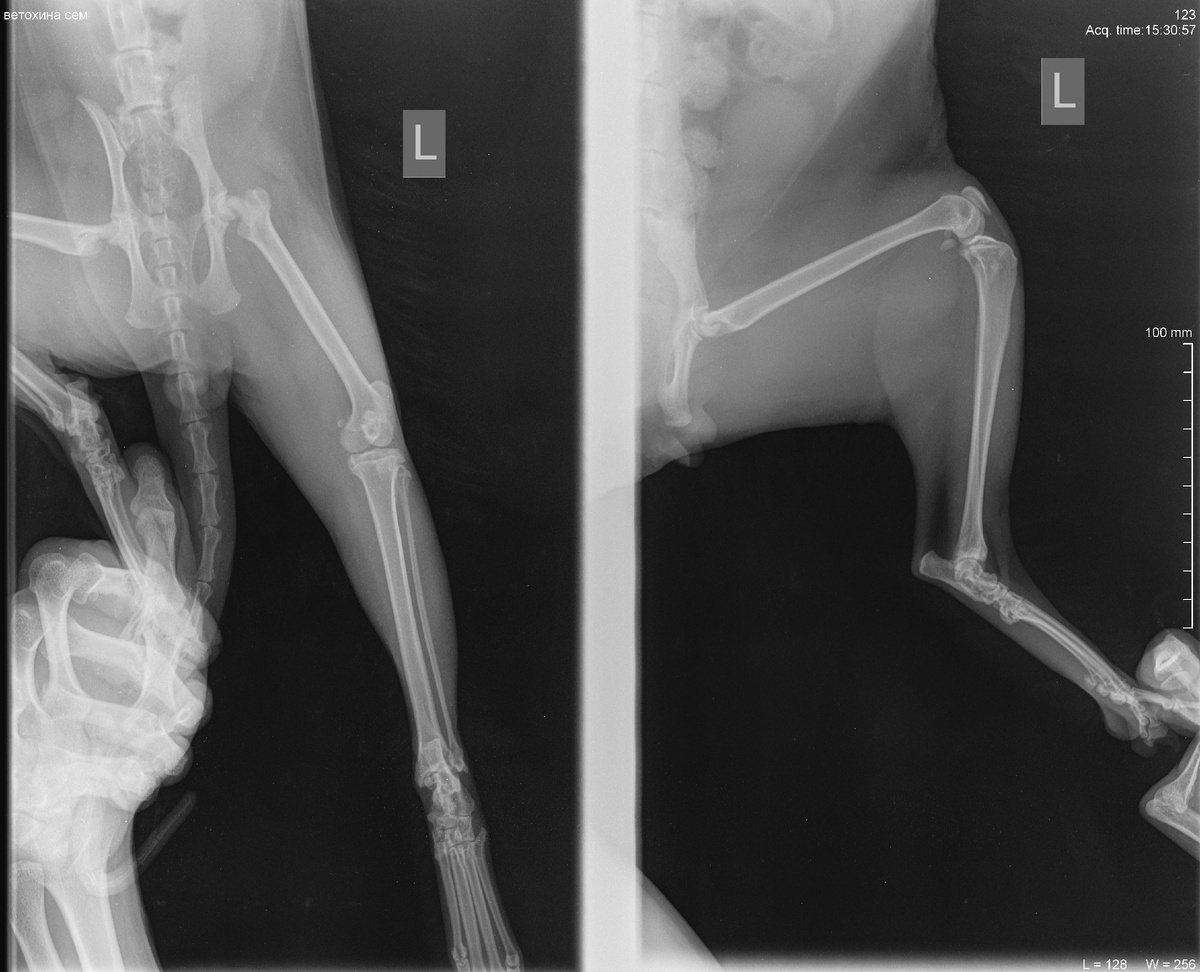

Записались на рентген, оказалось сломана шейка бедра слевой стороны. Только операция улучшит ситуацию. Если её не делать, кот останется инвалидом и дальше могут быть ухудшения.

рентген